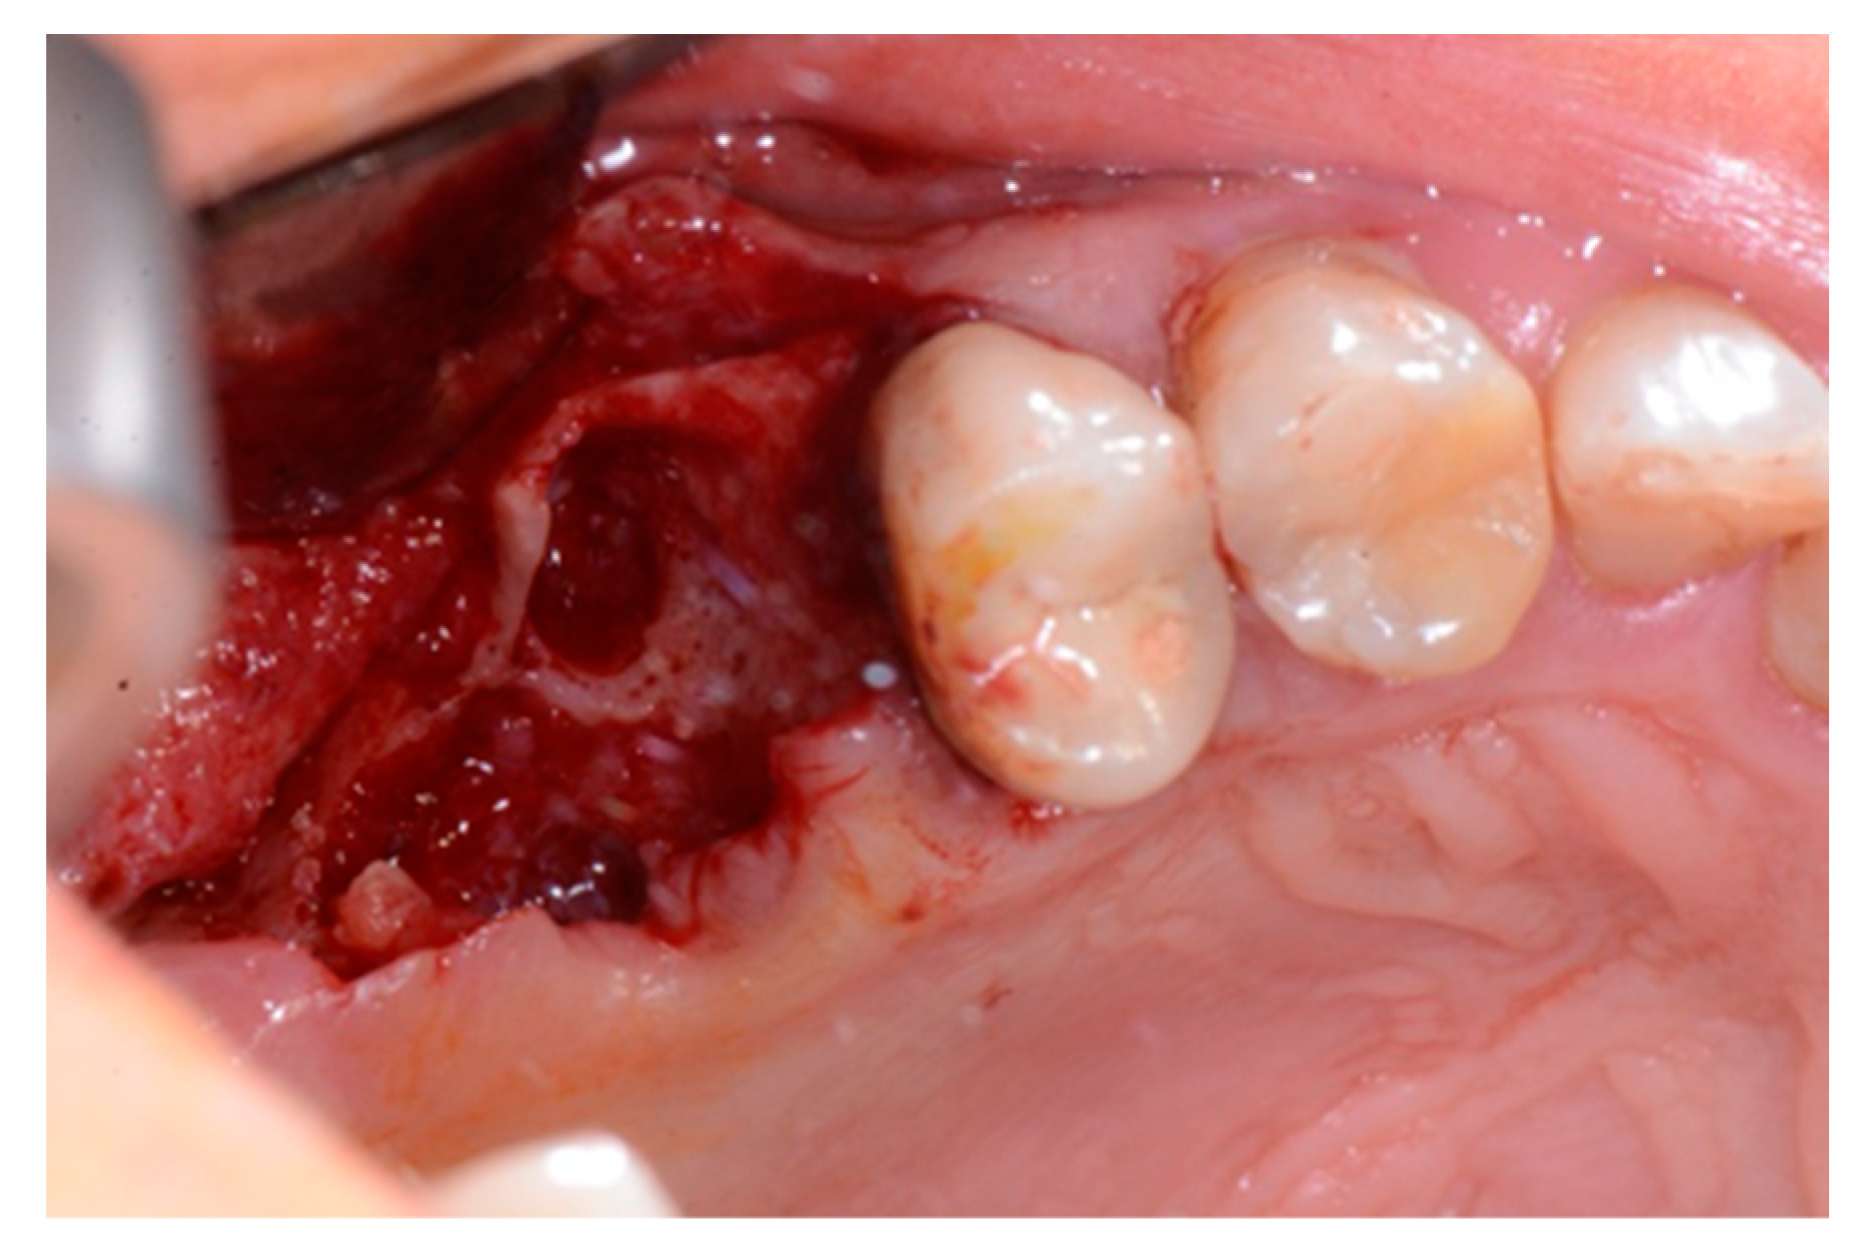

We used only surgical discarded material for the present study and the subject gave her informed consent before her participation. Seven days before the tooth extraction, the patient started prophylactic antibiotic therapy with amoxicillin/clavulanic acid (Augmentin, GlaxoSmithKline, Verona, Italy) and continued it for seven days after surgery 1 g/every 12 h, in addition to mouthwashes (chlorhexidine 0.2%) starting a week before surgery and continuing until healing occurred. Figure 2 shows the clinical situation after the crown removal. Once the extraction of tooth 26 (Figure 3) was carried out, the preservation of the alveolus was performed using a commercial enzymatically-deantigenated equine bone (Osteoxenon bone granules, Bioteck S.p.A, Vicenza, Italy) (Figure 4) and a commercial double layer of equine pericardium membrane (Heart pericardium membrane, Bioteck S.p.A., Vicenza, Italy) was used to cover and protect the site (Figure 5).

Figure 3.

Alveolar socket after the extraction of the roots.